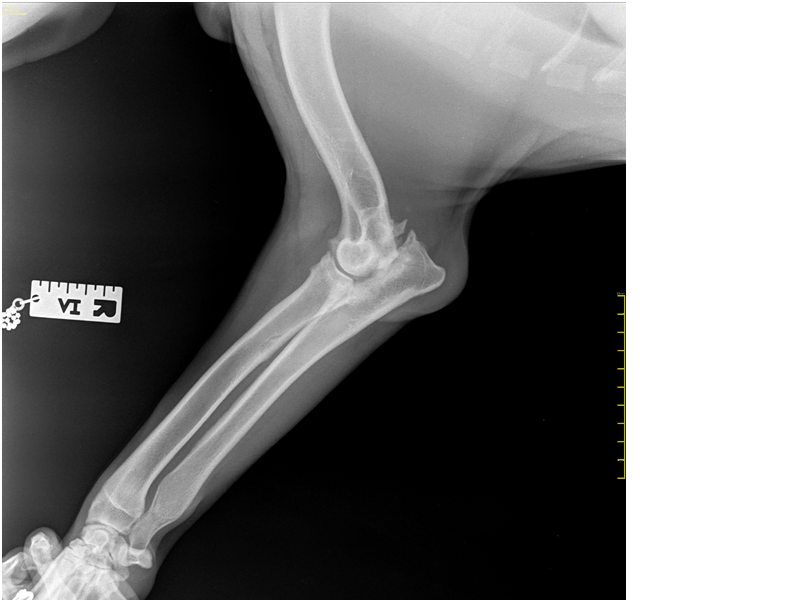

Рентгеновские снимки анатомии собак: строение и здоровье